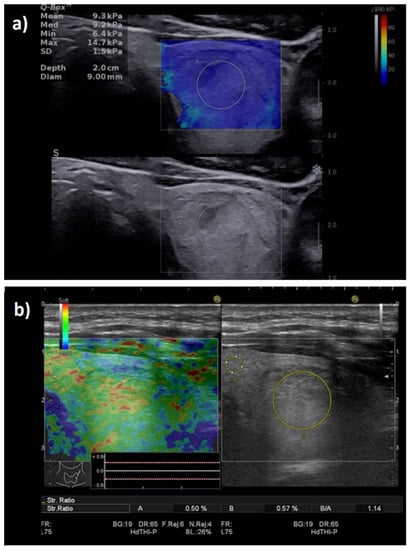

For the image acquisition, the box was adjusted to include the entire lesion. To acquire a stable, reliable elastogram, the examiner held the probe still for about 5 s and avoided applying external pressure. The machine does not provide a quality measure, so an experimented operator should perform the evaluation and avoid obtaining images with obvious compression artifacts such as “finger-like” artifacts or images with a completely red image (corresponding to high stiffness) []. Images lacking an SWE signal were also considered inadequate. The ROI was placed in the stiffest part of the nodule. The evaluation was uniform, and 5 values were registered for each lesion in longitudinal scans. The mean of the 5 measurements was considered in the analysis of the Max and Mean elasticity index (EI), measured in kPa. The QBox ratio was determined by comparing two ROIs, one in the stiffest displayed zone (without including obvious artifacts or calcifications inside the ROI) and one in the adjacent thyroid parenchyma or surrounding muscle, both placed at approximately the same depth, as shown in Figure 1. The diameter of the ROIs was set between 2–4 mm. Increased stiffness, documented by SWE evaluation, was considered as a high-risk parameter [,,,,].

Figure 1.

Transverse US scan displaying a soft thyroid nodule in the two-dimensional shear-wave elastography (2D-SWE) evaluation, first image (up): Mean elasticity index (EI) = 21.4 kPa, nodule-to-parenchyma QBox ratio = 1.3; and in the greyscale (2B) evaluation, second image (down): low-risk, isoechoic solid nodule, with a thin halo, well-defined borders, and no features of high risk.